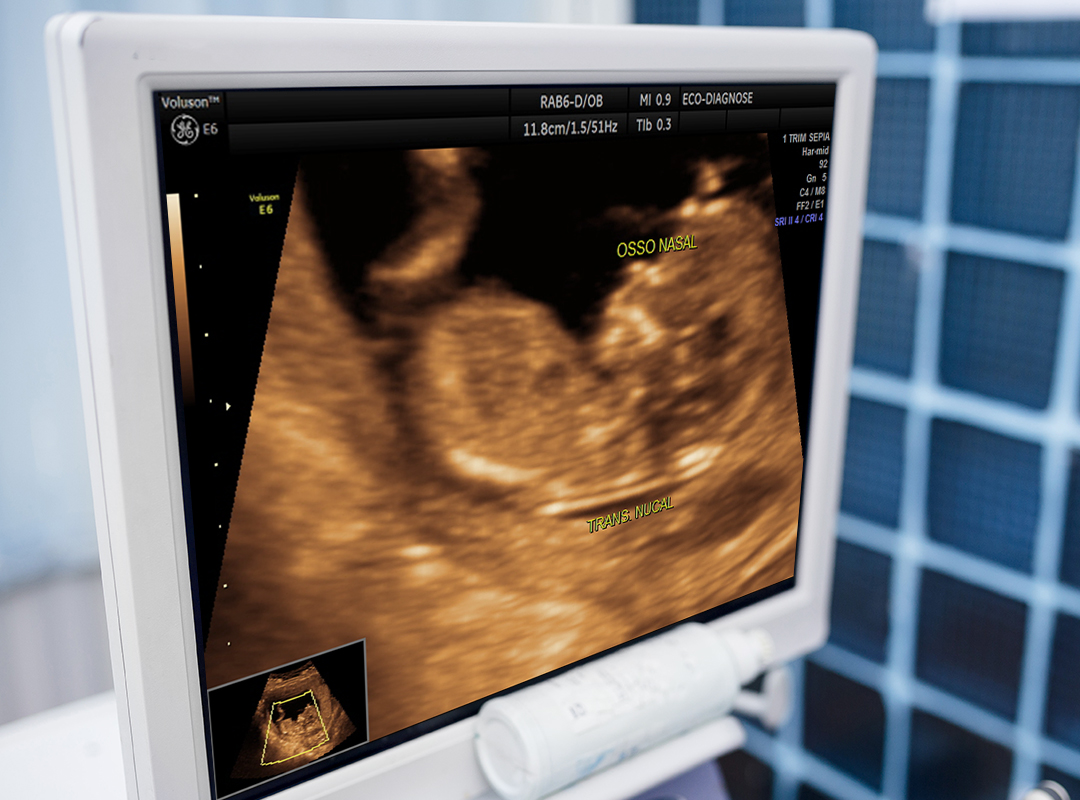

* Morfológico de primeiro trimestre (o exame mais importante no início da gestação)

Entre 11,5 e 13,5 semanas de gestação, temos um momento muito especial, aonde já somos capazes de avaliar alguns sinais (chamados marcadores), que tem por objetivo determinar o risco do feto ser portador de doenças cromossômicas e cardíacas.